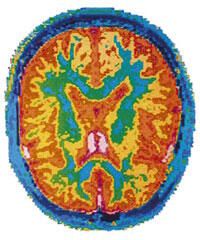

Les chercheurs affirment que les niveaux de testostérone diminuent naturellement avec les années, avec pour conséquence une augmentation du risque d'un certain nombre de maladies comme l'ostéoporose. Ce qui est moins clair, c'est de savoir si ces modifications hormonales normales pourraient également affecter le cerveau et augmenter le risque de développer une maladie d'Alzheimer.

Dans cette étude, des chercheurs ont comparé les niveaux de testostérone dans les tissus du cerveau d'hommes morts avec la maladie d'Alzheimer avec ceux d'hommes du même âge n'ayant pas souffert de cette maladie. Ils ont observé que les niveaux de testostérone étaient significativement plus faibles chez les hommes avec la maladie d'Alzheimer que chez ceux n'ayant pas eu cette maladie.

De plus, les niveaux de testostérone étaient aussi beaucoup plus faibles chez des hommes ayant les premiers symptômes de la maladie d'Alzheimer que chez ceux sans maladie.

Les chercheurs ont ainsi commenté ces résultats : «Nos travaux suggèrent fortement que la chute normale de testostérone liée à l'âge est un changement important qui favorise chez les hommes le développement de la maladie d'Alzheimer. Comprendre de quelle façon ces changements augmentent la vulnérabilité à cette maladie est très important non seulement pour expliquer le développement de la maladie d'Alzheimer mais aussi pour identifier les personnes à plus haut risque.»